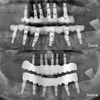

Implant tedavisi